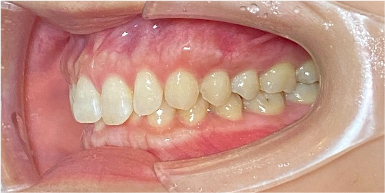

34歳女性のビフォーアフター

| 診断 | 叢生(デコボコがある状態)、開咬、下顎前突 |

|---|---|

| 治療方針 | インビザラインシステムにて主にIPR(歯と歯の間をわずかに削合してスペースを獲得する方法)を組み込んだ動的矯正治療を行った叢生改善と、開咬の改善のため臼歯部圧下をメインとした動的治療を行い、保定を行う。 |

| 治療費 ※ | 99万7千円(診断、型取り、PMTC、保定装置を含む料金) |

| 治療期間 | 3年5か月 |

| リスク | 1日20時間以上マウスピースを使用できない場合、歯が動かない可能性がある。装着時や食事時に痛みを伴う。歯肉退縮や虫歯になるおそれがある。また、指導通りに装着できていない場合や適切なブラッシングが出来ていないとそのリスクが高くなる。歯根が短くなることがある。ごくまれに歯の神経が損傷してしまうことがある。過去にぶつけたり深い虫歯治療をしたことがあるとそのリスクはやや高くなる。矯正後には保定装置が必要。適切な使用ができない場合、後戻りの原因となる。将来的に歯並びが動いて再矯正が必要な場合がある。舌癖が強い場合や正常に生えていない親知らずがある場合、その可能性が高くなる。 |

※ 治療費は、治療当時の費用で、現在の費用と異なる可能性があります。現在の費用は治療費のページでご確認くださいませ。